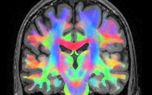

ظرفیت حافظه انسان معادل با حافظه ۳۱ هزار آیفون ۷s!